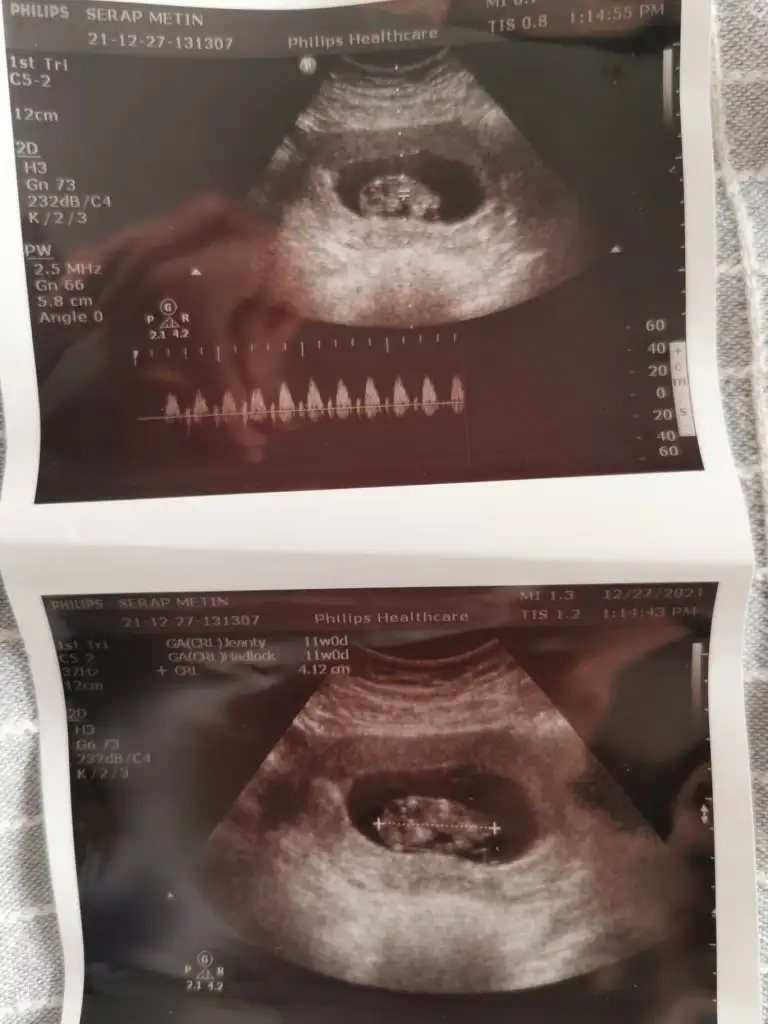

Merhaba,

Ikra meyra bir bakabilir misin. Kardeşim için 11 haftalık. Şimdiden teşekkürler.

Eklentiler

• IMG-20211227-WA0004.webp

30,5 KB · Görüntüleme: 53

• IMG-20211227-WA0008.webp

31,5 KB · Görüntüleme: 61

• IMG-20211227-WA0005.webp

17,5 KB · Görüntüleme: 55